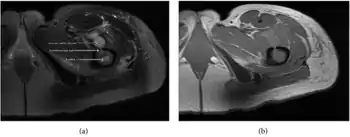

| a,b) MRI showing the Brodie's abscess in the left proximal femur | |

A Brodie abscess is a subacute osteomyelitis, which may persist for years before progressing to a chronic, frank osteomyelitis. Classically, this may present after progression to a draining abscess extending from the tibia out through the skin. Occasionally acute osteomyelitis may be contained to a localized area and walled off by fibrous and granulation tissue.

Oval, elliptical, or serpentine radiolucency usually greater than 1 cm surrounded by a heavily reactive sclerosis, granulation tissue, and a nidus often less than 1 cm. The margins often appear scalloped on radiograph. Brodie's abscess is best visualized using computed tomography (CT) scan. Associated atrophy of soft tissue near the site of infection and shortening of the affected bone. Osteoblastoma may be a classic sign for Brodie's abscess.

Periostial reaction along the medial cortex indicates an aggressive lesion. Neoplasm such as Ewing sarcoma and osteomyelitis could both have this plain radiographic appearance. Staphylococcus was recovered at surgery.